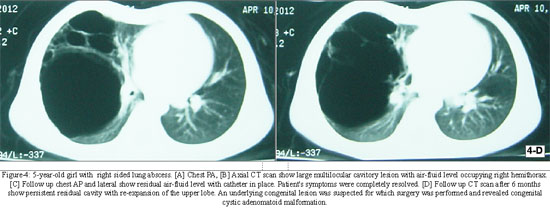

Two patients (10.52%) had residual cavity left and surgery was performed in both cases. Both of these cases were identified as congenital cystic adenomatoid malformation (CCAM).

In eleven out of nineteen patients, complete resolution of abscess cavity occurred in 4 weeks, whereas in four patients it took 5 weeks. In two patients abscess cavity persisted till 8 weeks till they were operated and histopathological examination of the excised tissue revealed congenital cystic adenomatoid malformation. Two (10.52%) out of nineteen patients developed persistent empyema, not resolving by pleural catheter drainage. These patients were ultimately operated and found to have bronchopleural fistula formation (Figures 1 to 4). No mortality occurred during or after procedure.